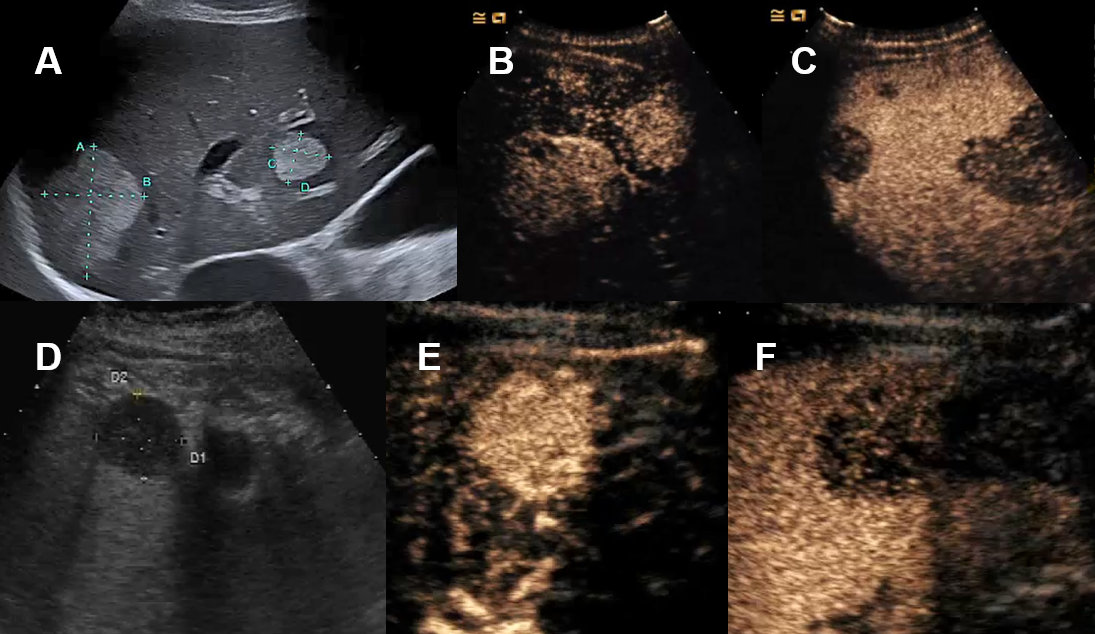

Conventional ultrasound is the first imaging modality to demonstrate fluid-containing lesion with smooth thin wall with a sensitivity and specificity of 90% [2, 9]. Simple liver cysts are non-enhancing on CEUS [3]. Septation, mural irregularity/mural nodularity or echoic internal material define a complex liver cyst needing further investigation. Vascular perfusion with septa or solid enhancing noduli of the liver cyst can be demonstrate or excluded by CEUS (figure 5). Alternatively, CT or MRI are very sensitive imaging modalities in this scenario.

Figure 5Liver cyst on ultrasound and CEUS. A Ultrasound with cystic lesion with echogenic content. B CEUS without contrast-enhancement demasking a complex hepatic cyst.